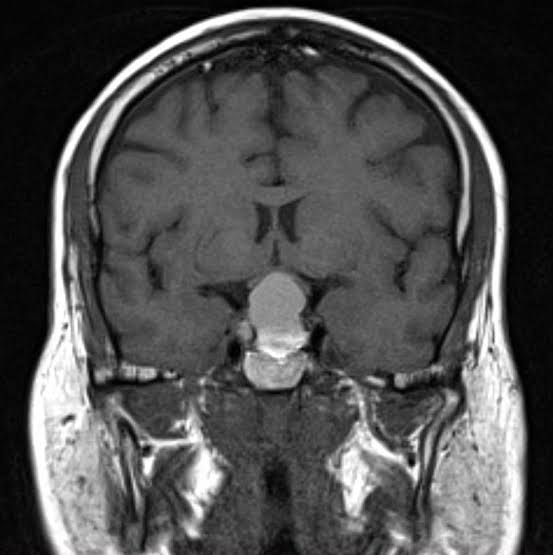

The diagnostic process for pituitary adenomas depends on what kind of adenoma you have and if it’s causing symptoms or not. If you have a hormone-secreting pituitary adenoma, your healthcare provider will likely diagnose you with the condition it causes based on your symptoms before diagnosing the adenoma. This is because many conditions that result from excess hormones can have many different causes — not just pituitary adenomas. This is also true of hypopituitarism (pituitary hormone deficiency) causes. Sometimes, healthcare providers find pituitary adenomas by accident when you get an imaging test of your brain for another condition. In these cases, the adenoma is usually small and nonfunctioning.